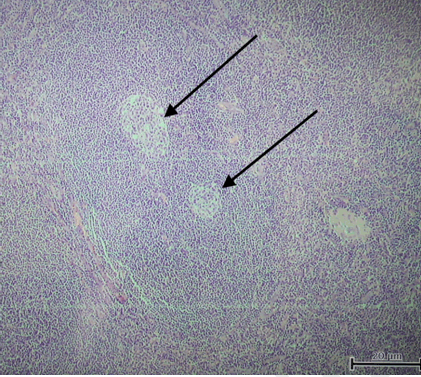

An 18-year-old female with no co-morbidities, presented with a swelling in the right side of the neck for the past two years, which had increased over the past one month. There was no pain over the swelling, no complaints of difficulty in eating or swallowing food. There was no history of fever, night sweats, or weight loss. There was no history of any other such swellings in any part of her body. Physical examination revealed a firm level II cervical lymph node in the right side of her neck. Contrast-enhanced computed tomography scan, of the neck showed a well-defined right cervical lymph node of 4 x 3 cm (Figure 1). She underwent excision biopsy of the lymph node at another institution and was referred to our center for further evaluation and management. Computed tomography scan of the thorax, abdomen and pelvis showed no other significant lymphadenopathy. HIV, HBsAg and Anti-HCV antibodies were negative. Bone marrow aspiration and biopsy were normal. Histopathology of the same showed a characteristic onion skin appearance of follicles with two germinal centres within the same follicle surrounded by a marked mantle layer hyperplasia (Figure 2). There was also presence of the pathognomonic "Lollipop Lesions" (Figure 3) which are formed due to penetration of sclerotic blood vessels into the atrophic germinal centers. These features were consistent with the diagnosis of the hyaline vascular variant of unicentric Castleman's disease. As whole node excision was done and she had no evidence of disease elsewhere in the body, she was kept under follow-up.

Figure 3: Classical 'Lollipop Lesion' (Black arrow) (H&E stain, x100).

The hyaline vascular variant of Castleman's disease is characterized by the presence of abnormal follicles with atrophic germinal centers surrounded by wide mantle zones consisting of small lymphocytes [2]. A characteristic feature is the presence of two adjacent germinal centers surrounded by a single, wide mantle zone. These are called double germinal centers. The germinal centers are usually depleted of lymphocytes and are replaced with follicular dendritic cells arranged in a concentric manner producing an onion-skin appearance (Figure 2). The interfollicular tissue contains many small sclerotic blood vessels These are often seen penetrating up to the centre of the regressed germinal centers, producing a pathognomonic "lollipop lesion" [1] [2] [13].